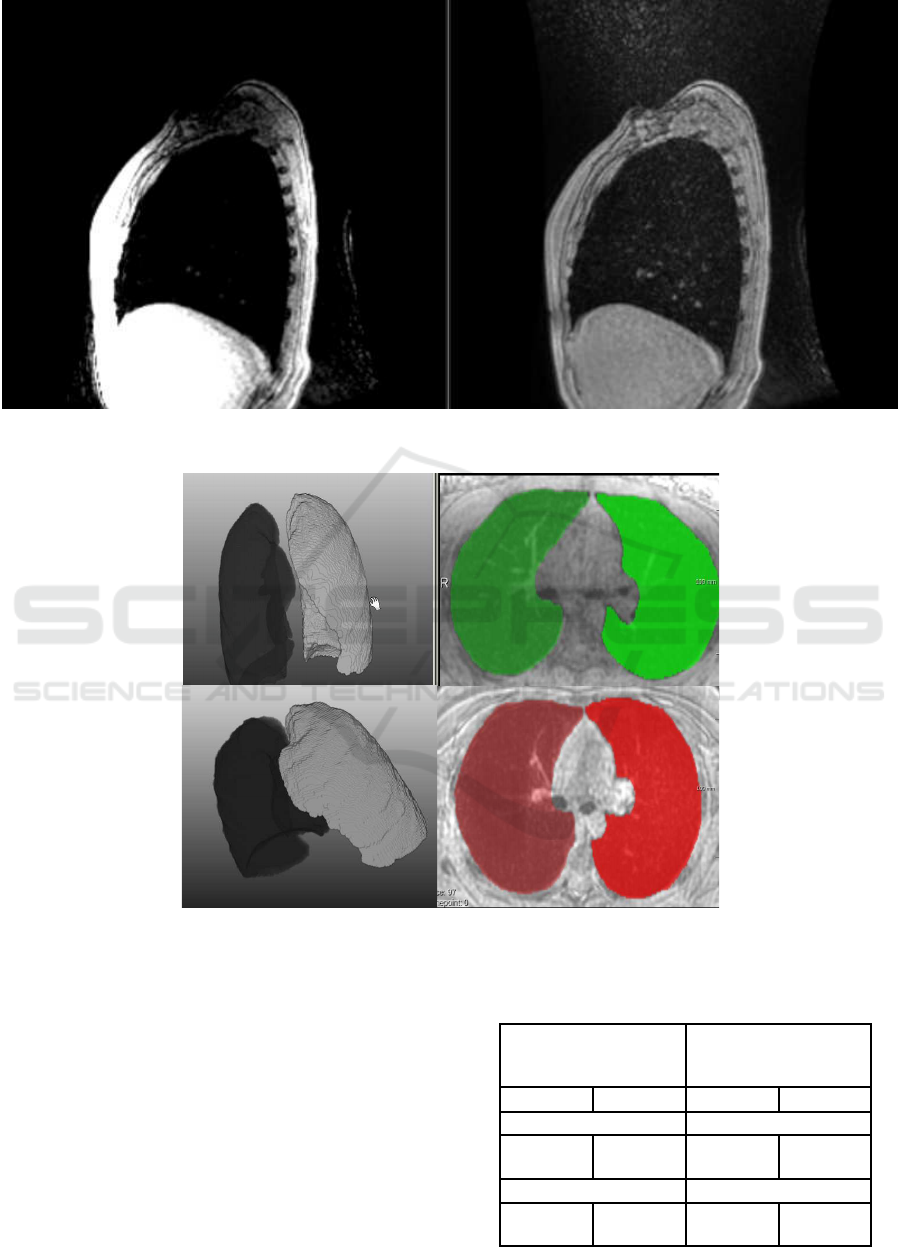

In Figure 3, we present 3D and 2D exam-

smoothed lungs.

Figure 2: Example slice in a sagittal view. Left: original data; Right: corrected data with three consecutive N4ITK cycles.

Figure 3: Example results from 2 datasets. Left: 3D results; Right: Segmentation results are overlaid with the original data in

axial projection.